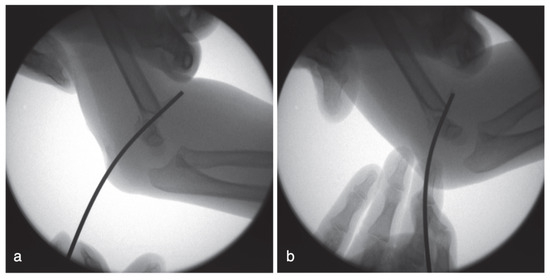

A Modified Technique for Medial Pin Placement in Pediatric Supracondylar Humerus Fractures

by Zhi-Kang Yao, Li-Kai Kuo and Wei-Ning Chang

Surg. Tech. Dev. 2025, 14(4), 36; https://doi.org/10.3390/std14040036 - 21 Oct 2025

Background: Displaced pediatric supracondylar humerus fractures (PSHFs) commonly require surgical treatment. Medial pin placement can cause iatrogenic ulnar nerve injury. This study presents a modified, step-by-step cross-pinning technique for PSHFs designed to avoid iatrogenic ulnar nerve injury. Methods: We retrospectively included [...] Read more.

Background: Displaced pediatric supracondylar humerus fractures (PSHFs) commonly require surgical treatment. Medial pin placement can cause iatrogenic ulnar nerve injury. This study presents a modified, step-by-step cross-pinning technique for PSHFs designed to avoid iatrogenic ulnar nerve injury. Methods: We retrospectively included patients with PSHF (Gartland types III or IV) who underwent closed reduction and percutaneous cross-pinning at our hospital from June 2014 to December 2024. Demographic data, fracture type, and preoperative and postoperative neurological deficits were recorded. Results: A total of 40 patients (16 boys and 24 girls) with a mean age of 6.6 ± 2.2 years (range, 2–14) were included. Most injuries were type III (35/40; 87.5%), whereas five patients (12.5%) had type IV injuries. Our technique resulted in no new cases of postoperative ulnar neuropathy. Conclusions: This study describes a modified medial pin insertion technique for unstable PSHFs. Careful attention to medial pin placement can minimize iatrogenic ulnar nerve injury. Full article